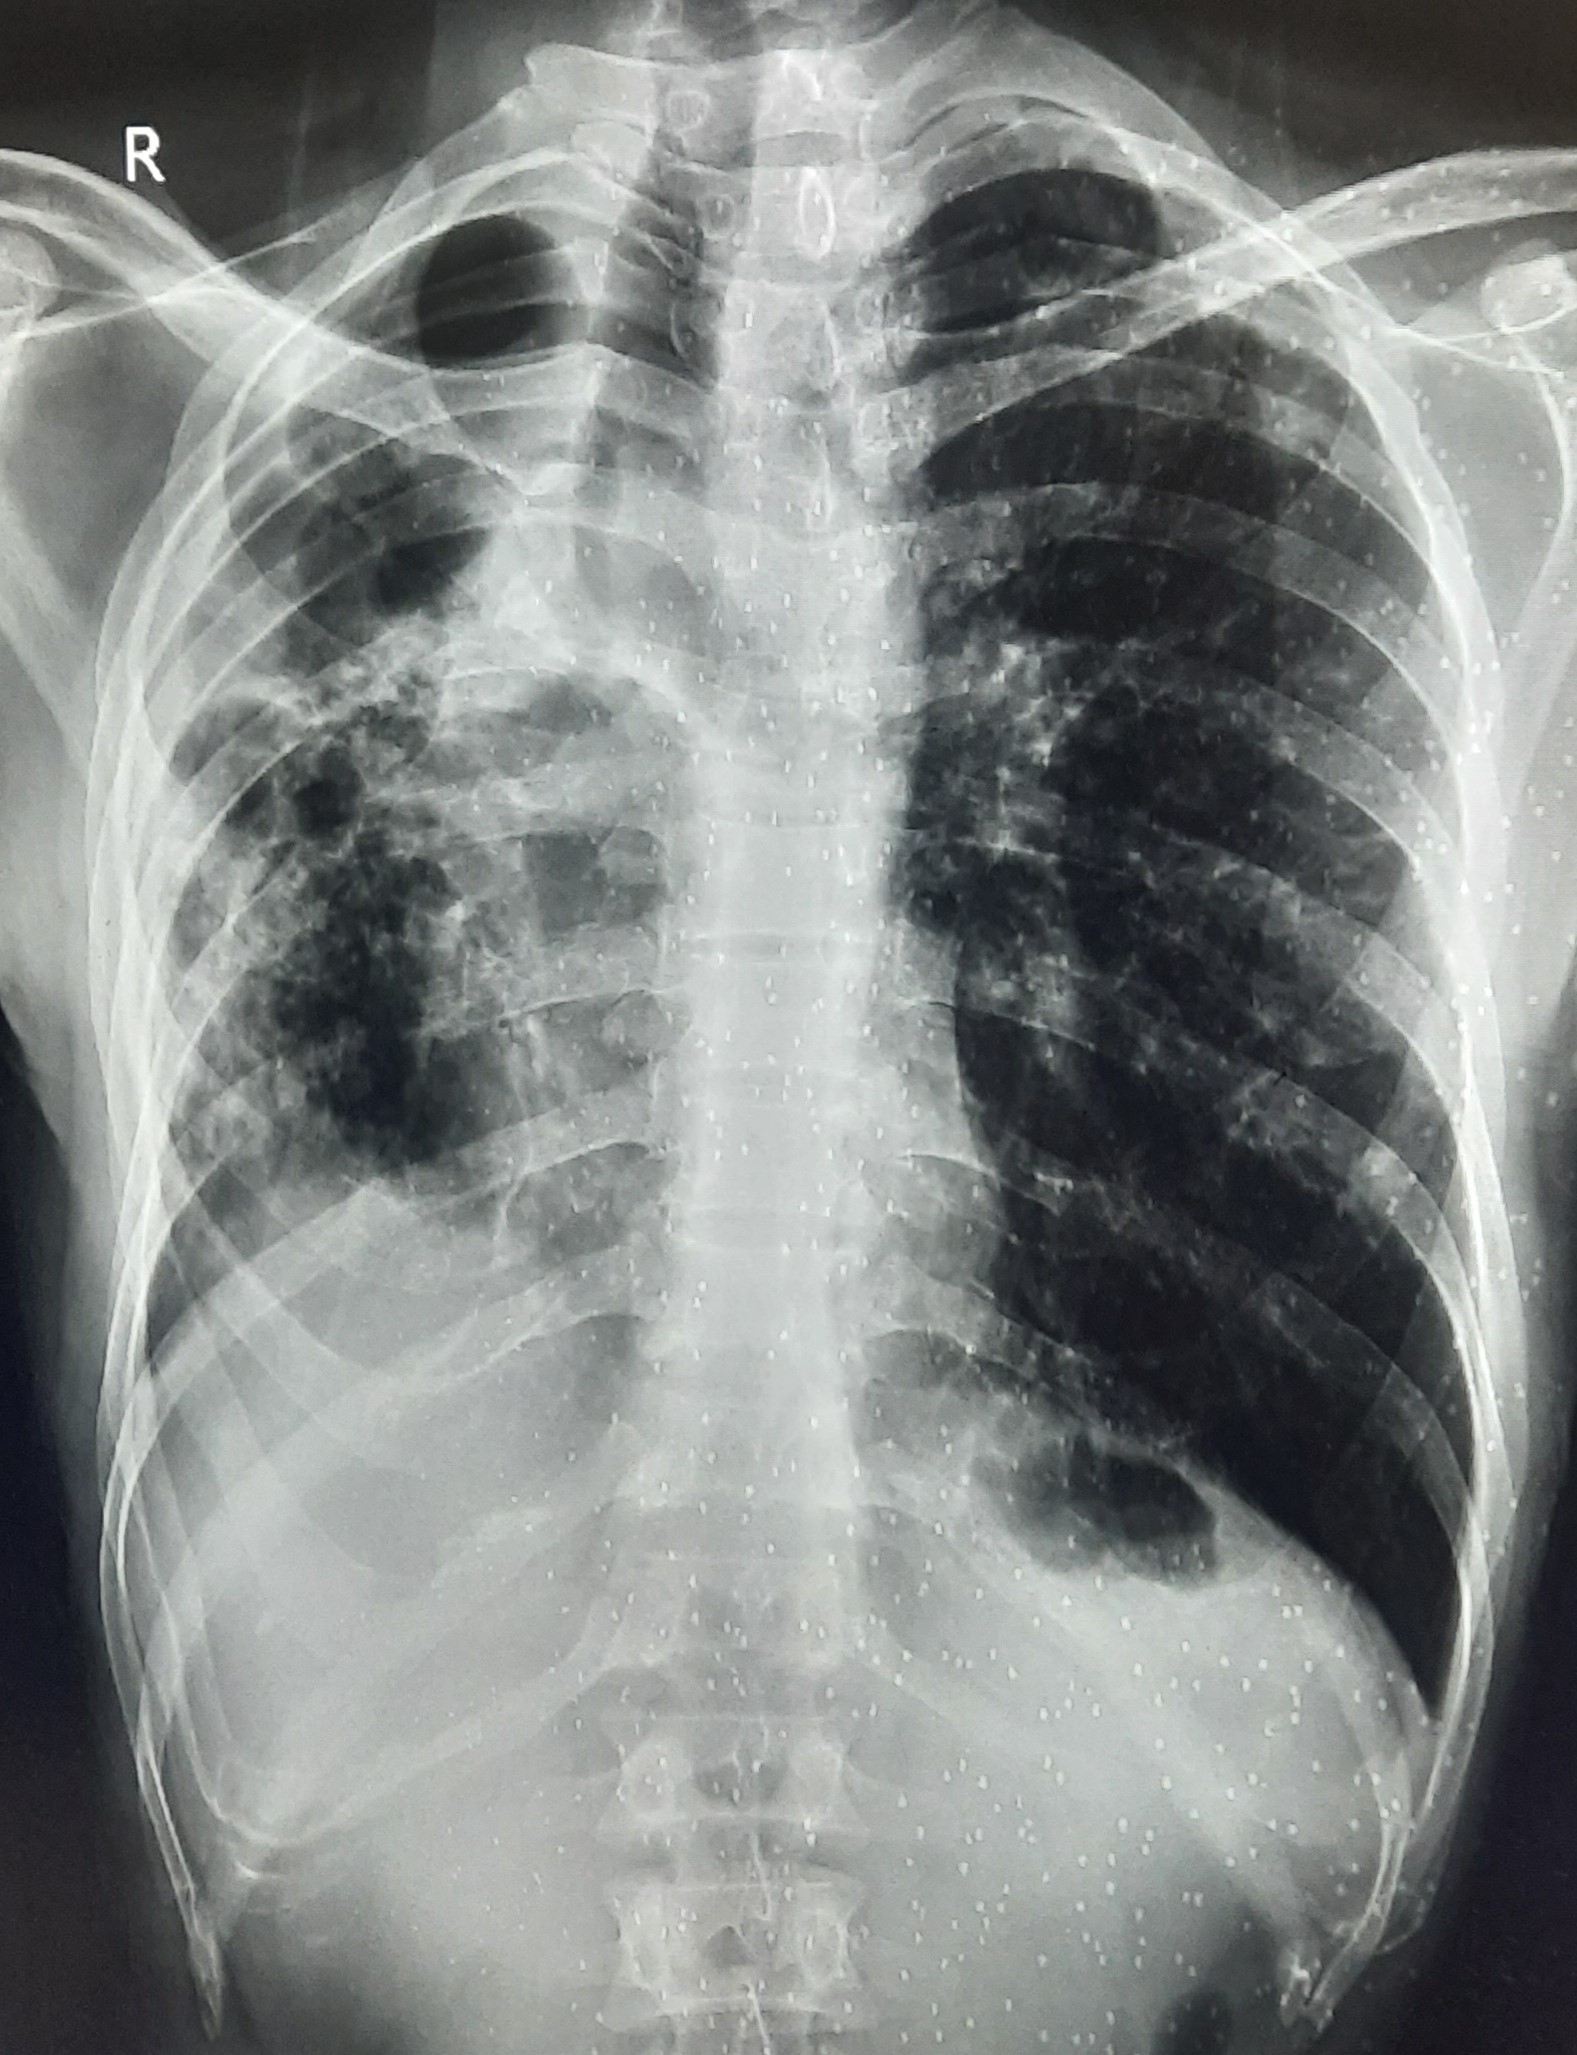

| 297 | IGGMC, Nagpur, Nagpur | P2 | 29-4175 | Sabina Parveen | Consent taken on Paper | 23 Yrs. |

Provisional Diag : PTB Reactivation

Final Diag : ? |

TB Case (Confirmed) | Bilateral Middle Lower Zone Pulmonary TB | Abnormality visible on x-ray |